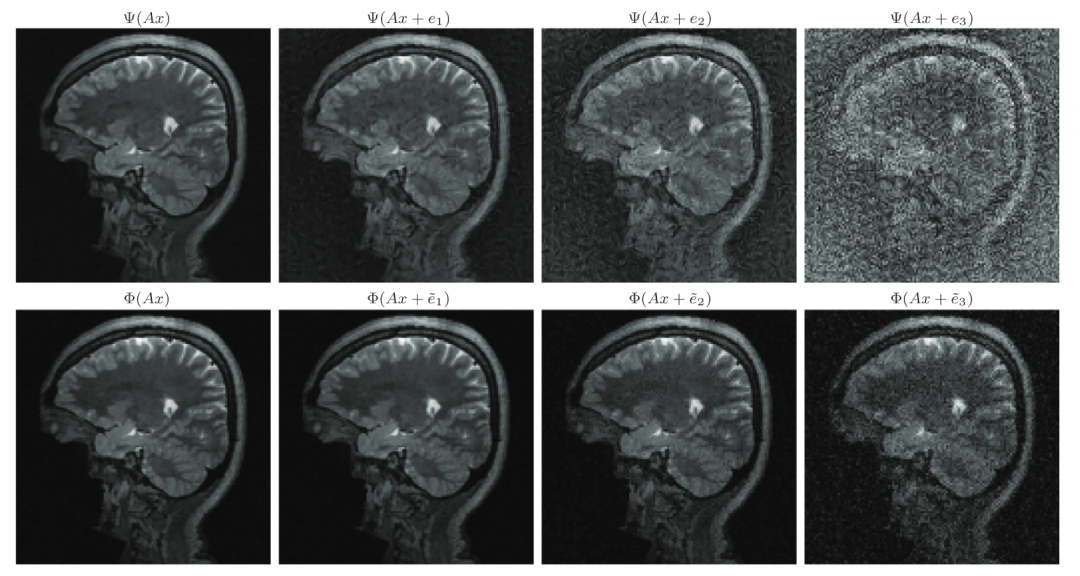

FIRENETs对扰动具有鲁棒性

在稳定性测试中,团队将 FIRENETs 与V. Antun等人(2020)开发的AUTOMAP网络进行对比。如下图中的上行所示,AUTOMAP网络重建很不稳定,导致图像完全变形。下行则是使用FIRENETs网络的重建结果。即使在最差的重建结果中,它仍然保持稳定。

这证明了由FIRENETs算法所计算的神经网络在小波中稀疏的图像中,在对抗扰动方面具有稳定性,而且同时能够维持一定的准确性。